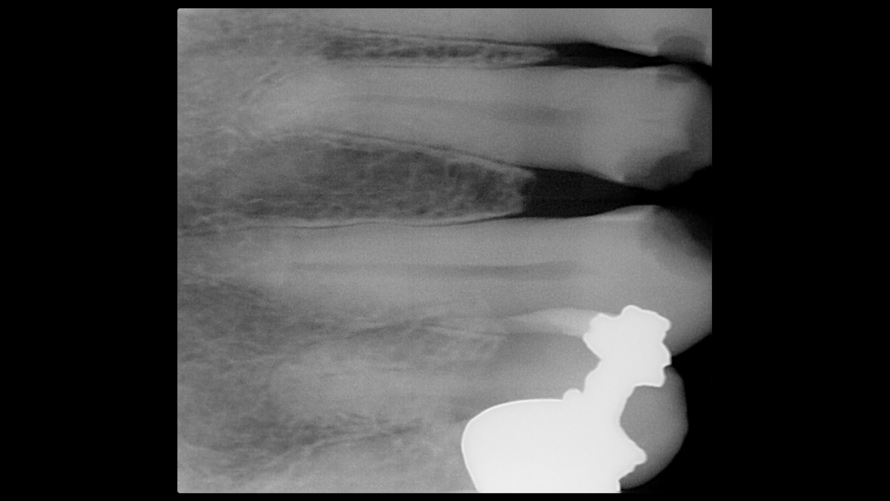

(14.) Photograph of fractured right lateral incisor taken with a smartphone and an EALS device during patient presentation for emergency treatment shown with accompanying radiograph.

Figure 14

(15.) Photograph of fractured right lateral incisor taken with a smartphone and an EALS device during patient presentation for emergency treatment shown with accompanying radiograph.

Figure 15